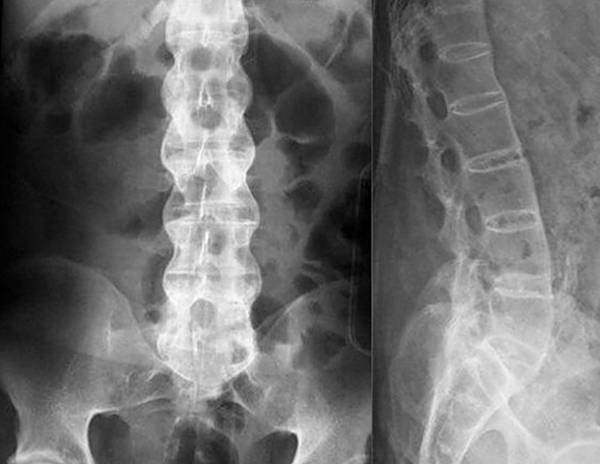

Если симптомы явно указывают на грыжу, остеохондроз или радикулит, для диагностики обычно применяют рентгенологическое исследование. Рентгенография относится к самым простым и доступным способам, к тому же, для снимка требуется совсем немного времени, в отличие от КТ, где пациент должен сохранять неподвижность достаточно долго. Для оценки состояния сосудов и мягких тканей назначают УЗИ, а при подозрении на инфекционную природу недуга обязательно проводятся лабораторные исследования крови и мочи. По полученным результатам врач подбирает больному оптимальный способ лечения.

При заболеваниях позвоночника чаще всего для диагностики применяют рентгенографию

Обнаружить протрузию и грыжу можно рентгенографическим исследованием, МРТ и КТ.

Обнаружить искривление позвоночника врач может после осмотра больного и на основании результатов рентгенографии.

Радикулит может быть диагностирован после проведения рентгенографического обследования. В некоторых случаях показано проведение МРТ или КТ.

Для диагностики используют рентген, КТ и МРТ.